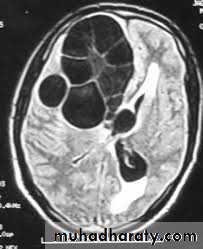

Hydatid cyst

CT Scane

Appear as large oval hypo dense area density of fluid with well defined margin , sometime at their periphery multiple flecks of calcification are seen at their periphery .

Hydatid cyst with daughter cyst , appear as multiple hypo densities rounded area within the main loculi with multiple rim of

calcification